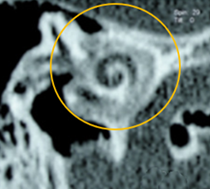

Figura 4. Vista de la ventana oval en un corte coronal del oído medio |

Tamaño del nicho de la ventana oval: Valores de 1,4 mm se toma como límite inferior de la normalidad. Valores menores se asociaban con un riesgo mayor de tener dificultades técnicas durante la cirugía del estribo. Debe descartarse una otosclerosis obliterativa (Fig. 4-5). |

La evaluación mediante tomografía es fundamental para identificar los focos otoscleróticos, principalmente en la ventana oval a nivel de la fissula antefenestran, la cual es un surco que se localiza entre la ventana oval y el proceso cocleariforme. En la fase otospongiótica o activa de la otosclerosis, se pueden observar áreas hipodensas en el hueso, mientras que en la fase inactiva otosclerótica, se observara hueso compacto que puede afectar progresivamente la platina del estribo, provocando la fijación de este.

El grosor normal de la ventana oval se establece en 1.64 mm; valores superiores a 3 mm son considerados compatibles con otosclerosis. En un bajo porcentaje, alrededor del 10%, se presenta un subtipo retrofenestral, que afecta la cápsula ótica y puede resultar en desmineralización, lo que se clasifica como "otosclerosis muy avanzada", según lo definido por House y Sheehy.93 A continuación, se detallan las diferentes clasificaciones relacionadas con esta patología (Tabla 2 y 3).